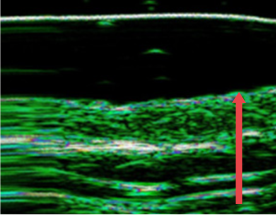

04. 피부 진피층 두께 변화

노화, 잦은 시술, 외부 자극으로 인해 얇아진 피부의 진피층을 개선합니다.

• radiesse_img11

시술 전

• radiesse_img12

4개월 후

(진피층 두께 12% 증가)

• radiesse_img13

7개월 후

(진피층 두께 27% 증가)